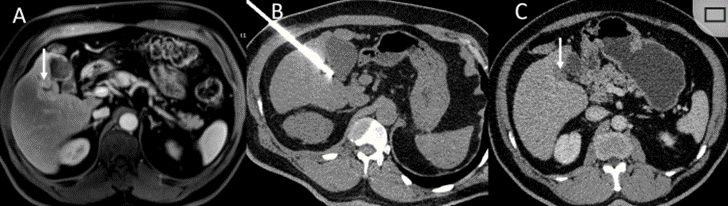

(9)直径> 5cm 的病灶,可通过多针穿刺和多点布针的方法尽可能适形、全面地消融病灶,也可根据情况行姑息性治疗,部分灭活肿瘤、减轻肿瘤负荷或延缓病情进展,以延长患者生存时间和提高生存质量。推荐方案是在消融后1 个月左右,复查动态增强CT 或MRI,或超声造影以评价消融效果,通过观察有无肿瘤残留,可分为完全消融及不完全消融。在肿瘤标志物检查中,原发性肝癌以血清甲胎蛋白水平作为评价指标,转移性肝癌多以癌胚抗原作为评价指标。治疗的不良反应主要有术后寒战发热、肝区疼痛、血清酶升高和血小板减少等,并发症包括感染、出血、胸腔积液、皮肤冻伤、肋间神经损伤、冷休克、胆瘘和肠瘘、肝功能衰竭等。充分术前准备、严格操作规范、准确定位与穿刺及术中动态监控是减少并发症发生率的重要方法。近年来,局部消融治疗得到广泛应用,其具有对肝功能影响少、创伤小、疗效确切、重复性好等特点。研究显示对于直径≤ 3cm 的肝细胞癌,局部消融与外科手术疗效无明显差异,冷冻消融使不适合手术切除的肝癌患者获得根治机会,现已是肝癌局部消融的常用方法。临床常见的原发性肝脏肿瘤是肝细胞癌,局部消融治疗现已是极早期和早期肝细胞癌患者治疗的一个组成部分。局部消融包括射频消融、微波消融和冷冻消融等。与其他方式相比,冷冻消融具有明显优点,包括影像监测冰球的边界、可激活有效的免疫效应、降低血管和其他关键结构损伤的发生率以及避免剧烈疼痛。本文探究了冷冻消融肝癌的临床有效性和安全性。回顾性纳入2018年10月至2019年8月期间接受冷冻消融手术的肝脏肿瘤患者9例, 5 名男性和 4 名女性。中位年龄为66 岁(范围:45-76 岁;平均年龄:62.4 岁)。其中7 例患者患有肝细胞癌,2 例患者患有肝转移癌。1例肝细胞癌患者有2个病灶,其余患者只有1个病灶。根据肿瘤位置,5个肿瘤位于胆囊附近,2个肿瘤位于右门静脉附近,2个肿瘤位于肝包膜附近,1个肿瘤位于胃附近。

(A)动脉期CT图像显示有一个包膜下结节(箭头)。(C) 在手术过程中的CT显示一个冷冻探针位于病灶内。随访时间中位数为7个月(范围:3-12个月),随访期间患者无局部肿瘤进展或死亡。

技术成功率为100%,本研究中77.8%(7/9)的患者达到了完全消融,辅助局部治疗后,所有患者均完全消融。

(A)门静脉期 CT 图像显示胆囊附近有病变(箭头)。(D)消融手术后 1 个月CT 显示完全消融。

本研究中患者随访期间无局部肿瘤进展,无死亡病例,没有发现与手术相关的并发症。证实冷冻消融是一种有效的治疗方式,在技术上是可行和安全的。由于肝包膜下病变位置特殊,射频消融有出血及肿瘤种植的风险,可能会对邻近器官造成损伤,并且增加局部肿瘤进展的风险。近年来,冷冻消融术的应用逐渐广泛,有研究显示冷冻消融治疗具有明显优势,可治疗特殊部位的肝肿瘤。本研究的目的是评价冷冻消融治疗肝包膜下肿瘤的安全性和有效性。回顾性纳入2016年7月1日至2018年9月1日期间冷冻消融的57例患者。包括42例男性和15例女性,平均年龄为62.4岁(范围:48-82岁)。每个患者有1个或2个平均肿瘤尺寸为2.4cm的病变(范围:0.6-4.0cm)。所有患者均患有慢性肝病或肝硬化,并伴有乙型肝炎(n=52)、丙型肝炎(n=3)和其他肝炎(n=2)。根据肿瘤位置,在膈肌或肝脏下附近有18个病变(26.5%),胃或肠附近有9个病变(13.2%),腹壁附近有33个病变(48.5%),肾脏附近有8个病变(11.8%)。